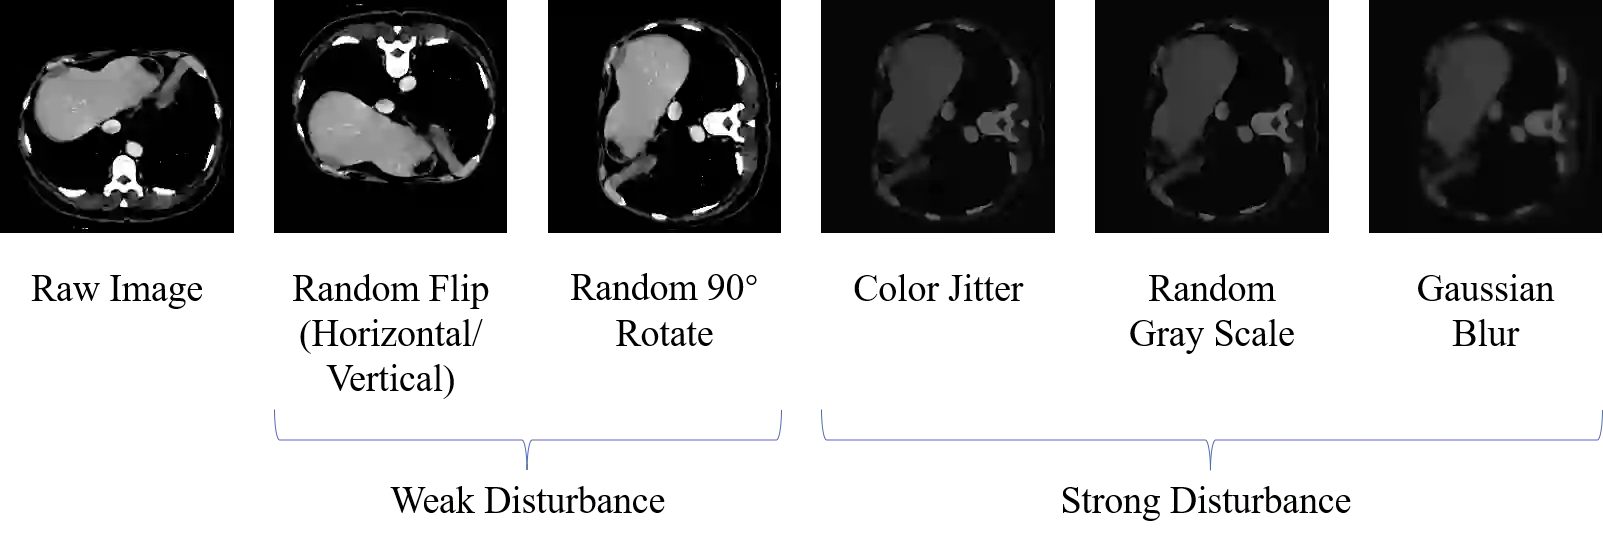

Machine learning models for medical images can help physicians diagnose and manage diseases. However, due to the fact that medical image annotation requires a great deal of manpower and expertise, as well as the fact that clinical departments perform image annotation based on task orientation, there is the problem of having fewer medical image annotation data with more unlabeled data and having many datasets that annotate only a single organ. In this paper, we present UniMOS, the first universal framework for achieving the utilization of fully and partially labeled images as well as unlabeled images. Specifically, we construct a Multi-Organ Segmentation (MOS) module over fully/partially labeled data as the basenet and designed a new target adaptive loss. Furthermore, we incorporate a semi-supervised training module that combines consistent regularization and pseudolabeling techniques on unlabeled data, which significantly improves the segmentation of unlabeled data. Experiments show that the framework exhibits excellent performance in several medical image segmentation tasks compared to other advanced methods, and also significantly improves data utilization and reduces annotation cost. Code and models are available at: https://github.com/lw8807001/UniMOS.